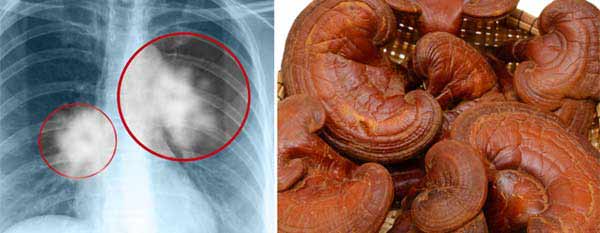

Reishi goba pomaga braniti pred rastjo rakavih celic

Tako kot druga protivnetna živila reishi gobe vsebujejo več vrst pomembnih protirakavih hranil, vključno z antioksidanti (polisaharidi in triterpenoidi), beta-glukani in aminokisline. Raziskovalci verjamejo, da je eden izmed najbolj koristnih sestavin gobe rezhi njeni polisaharidi, ki so v vodi topne vrste hranil, ki jih najdemo v živilih ogljikovih hidratov, za katera je znano, da imajo antitumorske sposobnosti.

• Polisaharidi, ki jih najdemo tudi v drugih koristnih rastlinskih živilih, kot so sladki krompir ali pesa, so skupaj s triterpenoidi imunsko modulirane snovi, ki zdijo, da branijo DNK in prekinjajo mutacije celic, hkrati pa ščitijo zdrave celice. Po nekaterih študijah nekatere zdravilne gobe pomagajo pri boju proti raku, saj imajo polisaharidi pomembne biološke koristi, vključno z antioksidantnimi, nevrozaščitnimi, radiozaščitnimi, proti diabetičnimi, antiosteoporoznimi in pomagajo proti utrujenosti.

• Poleg tega so laboratorijski testi pokazali, da imajo triterpeni lastnosti za boj proti rakavim celicam. Zdi se, da triterpenske spojine zavirajo invazijo tumorja in metastaze z omejevanjem vezave rakavih celic na endotelne celice. Beta-glukani so tudi naravni bojevalci proti raku, saj ustavijo rast in širjenje rakavih celic, medtem ko povzročajo, da imunski sistem postane bolj aktiven.

• Gobe Reishi se uspešno uporabljajo za boj proti raku dojk, jajčnikov, prostate, jeter in pljuč, včasih v kombinaciji z drugimi zdravljenji. Za bolnike, ki se zdravijo zaradi raka ali kemoterapije in zdravljenja s sevanjem, ima reishi zaščitne učinke, ki lahko naredijo zdravljenje bolj učinkovito.

• Raziskave pri bolnikih z rakom kažejo, da ima reishi antiproliferativne in kemopreventivne učinke, saj pomaga ublažiti neželene učinke kemoterapije, kot so nizka imunost in slabost in potencialno izboljša učinkovitost radioterapije – po mnenju mnogih so reishi gobe eno najmočnejših živil, ki so na voljo za boj proti raku.